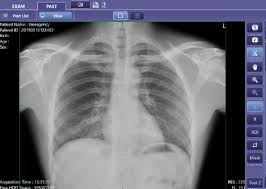

The Delft Light was designed for chest X-rays, but it can also image extremities and diagnose injuries and fractures. The 360-degree rotation of the X-ray tube stand allows for screening various body parts. whether the patient is standing or lying down.

Procuring Delft’s X-ray systems with CAD4TB simplifies project management with integrated training, installation, and support. CAD4TB is an AI software that analyses digital chest X-ray images to find TB-related abnormalities, as well as other lung and cardiac abnormalities. This strengthens the diagnostic value of chest X-rays in resource-constrained settings. Additionally, as a total solution provider for TB screening, we offer our clients a single point of contact for streamlined delivery, after-sales, and maintenance, reducing the total cost ownership and enhancing productivity and impact.